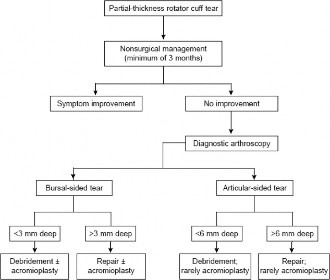

The correct answer is (C). Although treatment algorithms are debated, a generally accepted rule is that with chronic, rotator cuff tears, if the tear does not respond to a

trial of conservative treatment, operative treatment is warranted. For partial-thickness tears, the type of operation that should be performed is often controversial. One useful decision-making tool for patients with partial-thickness tears is the Ellman classification.

The Ellman classification differentiates between bursal-sided tears (Ellman classification B) and articular-sided tears (Ellman classification A), and also between those that are less than 3 mm in depth (Ellman classification I), between 3 and 6 mm in depth (Ellman classification II), and greater than 6 mm in depth (Ellman classification III). If a tear is bursal-sided and less than 3 mm in depth (BI), this can be treated with arthroscopic debridement of the tear (Answer A). If it is bursal-sided and greater than 3 mm in depth (BII as in this patient or BIII), this should be treated with arthroscopic rotator cuff repair (Answer C). In addition, subacromial decompression should be considered with all bursal-sided tears, and acromioplasty should be performed if the patient has a type II or type III acromion or has anterior acromion bone spurs. If the tear is articular-sided and less than 6 mm (Ellman classification AI or AII), this can be debrided. If the tear is articular-sided and greater than 6 mm in depth (Ellman classification AIII), this should be repaired. Subacromial decompression and acromioplasty may not be necessary in the case of articular-sided tears. Refer to Table 2–1 and Figure 2–10 for a summary of the Ellman classifications and the indicated surgical treatment after failure of conservative treatment.

Figure 2–10 Potential treatment algorithm for partial-thickness rotator cuff tears. (Reproduced with permission from Shi LL, Mullen MG, Freehill MT, et al. Accuracy of Long Head of the Biceps Subluxation as a Predictor for Subscapularis Tears. Arthroscopy 2015;32(4):615-619.)